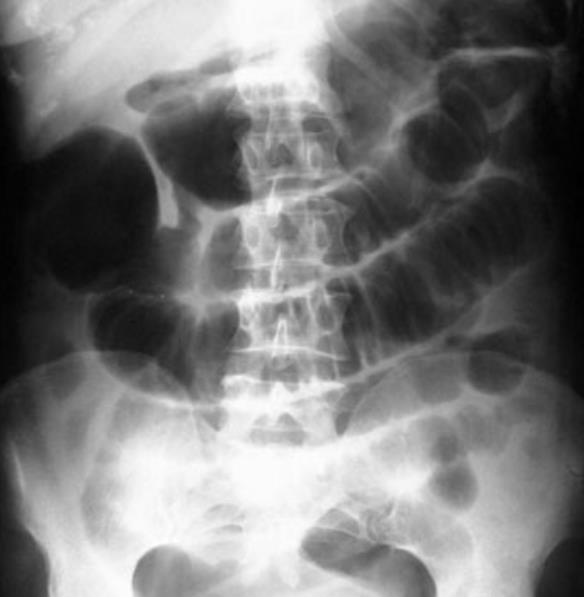

后来,腹痛越来越严重,就去301医院查体。

医生发现陈毅的腹部有硬块,怀疑是阑尾炎,于是安排陈毅割阑尾。

不负责任的301医院,拍了片子都能误诊,动手术一刀切下去才发现是肠癌,还是晚期了。

其实,当时拍的片子就能看出来陈毅是得了癌症,只不过医院不负责任,没有仔细诊断。

叶剑英亲自查看陈毅的病例,并把X光的片子放在墙上亲自过问。

他正颜厉色地让医生仔细看这些病例,是否能看出有癌症。